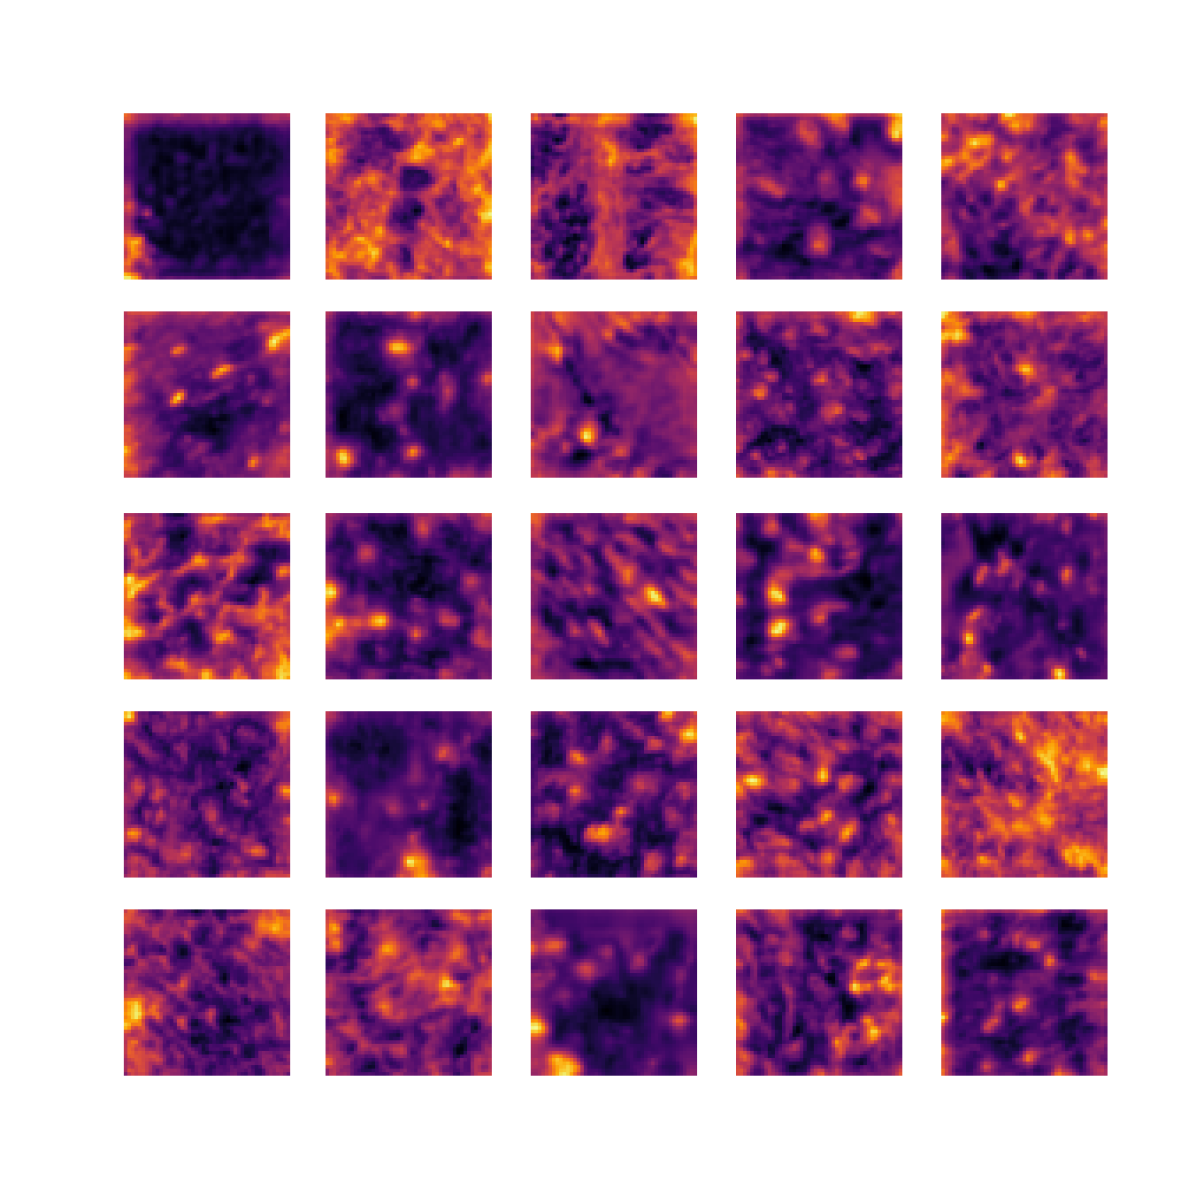

We also analyse the activation maps for each model using GradCAM as described in section S3. This offers more insight into the areas of the image which are contributing most heavily to the models’ representations. In Figure 4(b) we present some representative examples, however, a larger selection which was chosen at random is presented in Figures S10 to S25. The larger selection makes it easier to see the emergent patterns, including that privileged Siamese models tend to mainly identify features which are strongly present in both inputs, while unprivileged Siamese models tend to learn more diffuse features that are not specific to one cell phenotype or image region. TriDeNT ♆ incorporates both sets of features, learning both features specific to the privileged data and more the general features associated with unprivileged Siamese networks.

We can see in Figure 4(b) panel A that for ERG, the privileged Siamese model focuses almost exclusively on any nuclei which could be endothelial cells. As there are very few endothelial cells in the dataset, it could be an effective strategy to identify anything that could potentially be an endothelial cell to minimise the difference between the representations of the H&E model and the IF mask model. In the corresponding unprivileged Siamese image, we see that the model identifies some of these nuclei, albeit less strongly, but also focuses heavily on the other tissue and even the background, while strongly fixating on two spots of debris in the center of the image. This model has less ‘incentive’ to learn the weak features related to endothelial cells as these occur rarely and are not easy to detect, while more generic strong features such as the presence of connective tissue and the prevalence of background are more common and predictable from augmented images. We see that TriDeNT ♆ combines these two feature sets, strongly identifying nuclei while also identifying the connective tissue.

In panel C we see a similar pattern, with the privileged Siamese model fixating solely on the nuclei, while the TriDeNT ♆ model takes a more balanced approach. The unprivileged Siamese model appears to focus on a single cluster of nuclei while neglecting others, and similarly identifies an area of fibroblasts with its distinctive pattern but does not others.

In contrast to panels A and C which represent models with poor privileged Siamese results, panels B and D represent models whose privileged Siamese results were comparable to both TriDeNT ♆ and even the supervised baseline. It is therefore interesting to note that there are far more similarities between the privileged Siamese and TriDeNT ♆ models in both cases. Particularly in panel B, TriDeNT ♆ and the privileged Siamese model return virtually identical heatmaps, with both strongly identifying epithelial nuclei and neglecting the same areas of connective tissue. The unprivileged model in this case appears to focus solely on the centre of the image, giving a significantly different heatmap to the other panels.

Panel D again shows the previous pattern, with the privileged Siamese model identifying the features strongly present in the privileged data – fibroblasts – while neglecting the nuclei present. TriDeNT ♆ also strongly identifies the connective tissue, but, unlike the privileged Siamese model, does not completely neglect the nuclei. The unprivileged Siamese model primarily identifies background, and does not appear to identify the nuclei in this example.